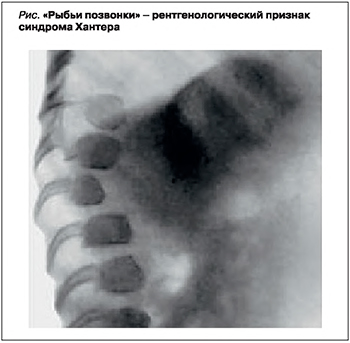

Диагноз «синдром Хантера» ставится на основании клинико-генеалогических данных (отягощенная наследственность, мужской пол, «гурлерподобный» фенотип, постепенно нарастающие изменения) и результатов лабораторных и инструментальных методов исследования [9]. На электрокардиограмме (ЭКГ) выявляются неспецифические изменения – снижение вольтажа желудочковых комплексов QRS. При рентгенологическом исследовании обнаруживаются небольшие сужения проксимальных отделов пястных костей и гипоплазия ногтевых фаланг кистей, признаки раннего окостенения затылочно-теменного шва и так называемые рыбьи позвонки (рис.) [9, 10].